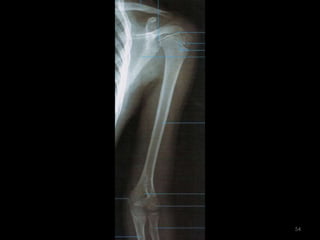

úmero51

Incidência AP Úmero52

53

54

Incidência lateral do úmero55